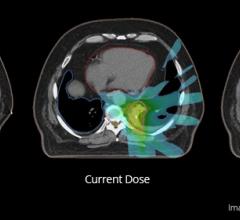

Monaco 5, the latest version of Elekta's Monaco treatment planning system has received 510(k) clearance from the US Food ...

Treatment planning systems have been an integral part of radiation therapy since the 1980s; however, today’s systems are ...